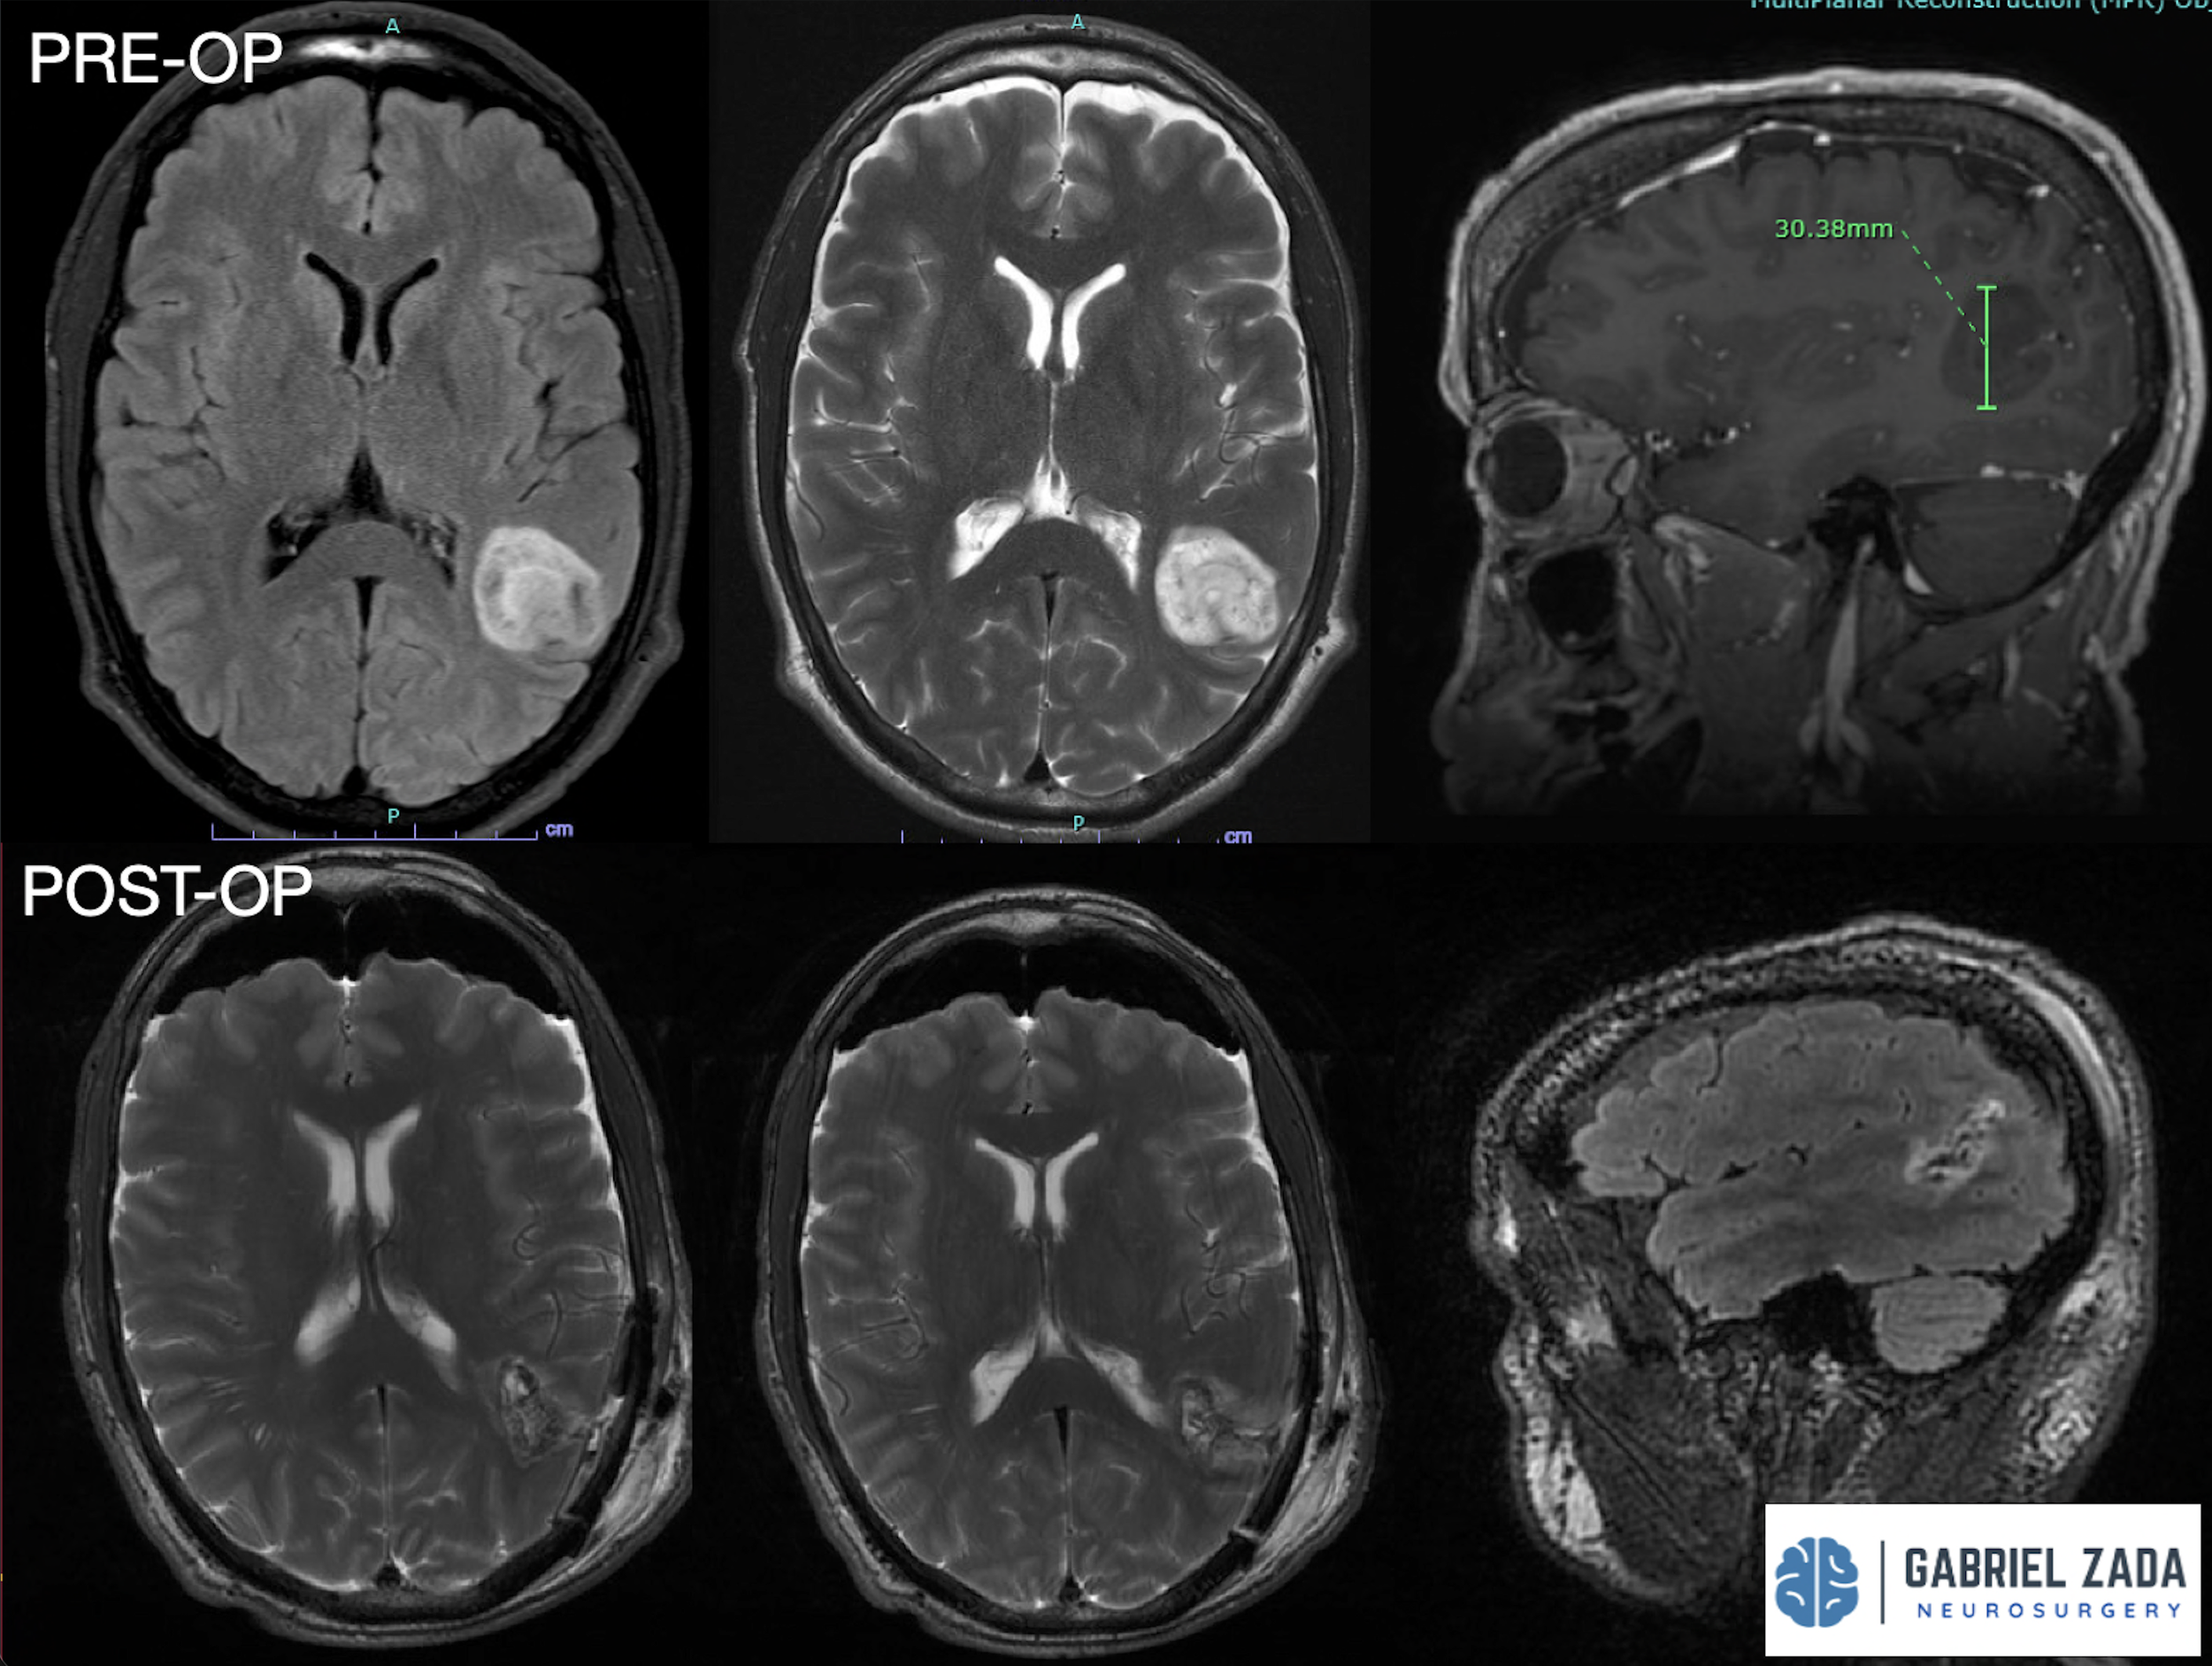

Explore this comprehensive gallery featuring pre‑ and post‑operative imaging of patients with skull‑base tumors treated by Gabriel Zada, MD, MS, FAANS, FACS. These cases highlight Dr. Zada’s expertise in advanced neurosurgical techniques and outcomes.

*Representative cases shown for educational purposes. All images de-identified. Individual results vary.